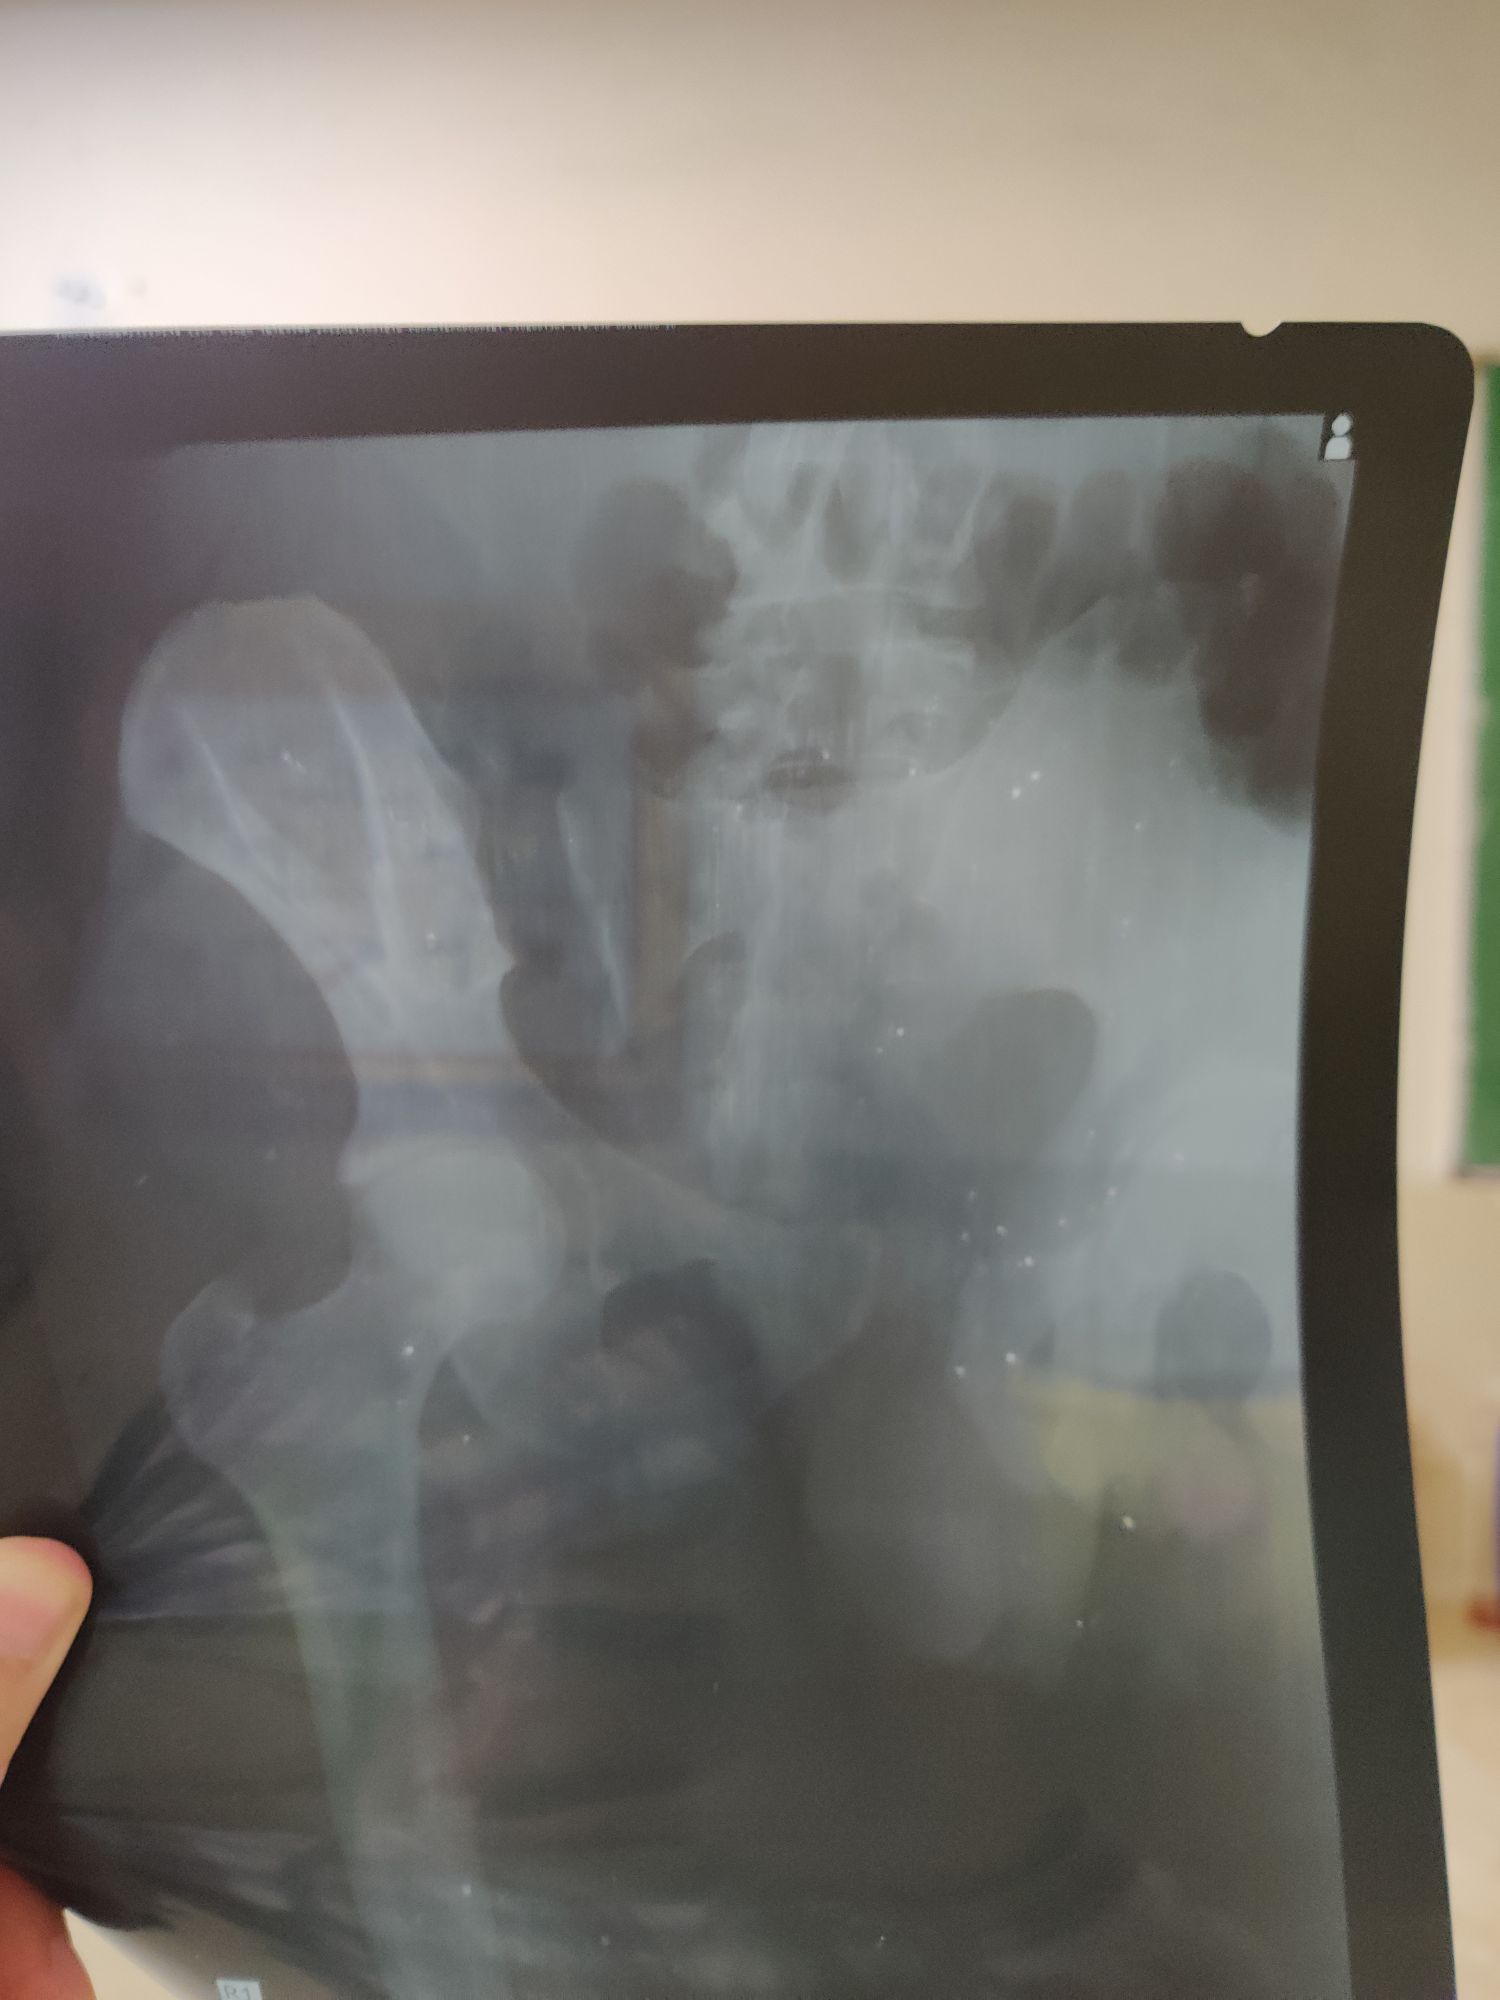

Sacroiliac Joint dislocation ?

Bones

Er

Rta